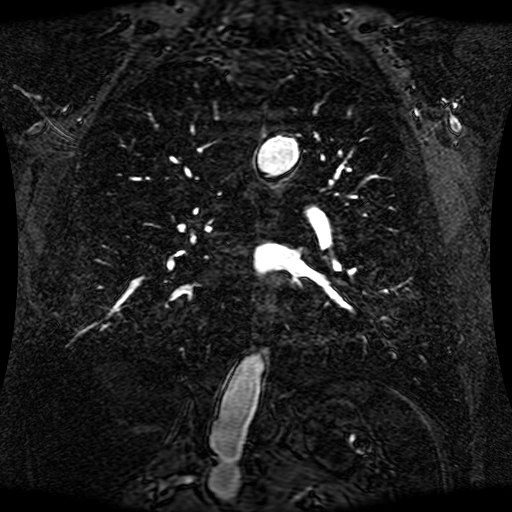

These magnetic resonance angiography (MRA) images show coronal slices acquired from consecutive anteroposterior positions within the torso. The study was performed on a 1.5T General Electric (GE) Signa imaging system with gadolinium-contrast-enhancement for visualization of the cardiopulmonary vasculature. The pulse sequence used was a 3D time-of-flight fast spoiled gradient recalled acquisition in steady state (FSPGR, TR=6.3, TE=1.4, NEX=1, FOV = 40cm, slice thickness = 1.2mm).

This sample image contains 76 frames. It is available in DICOM format (E1154S7I.dcm), as an animated GIF (E1154S7I.gif), as .ogg, .mp4, .webm, and .swf animations (one of which is shown above), or as individual PNG-format frames (see below).